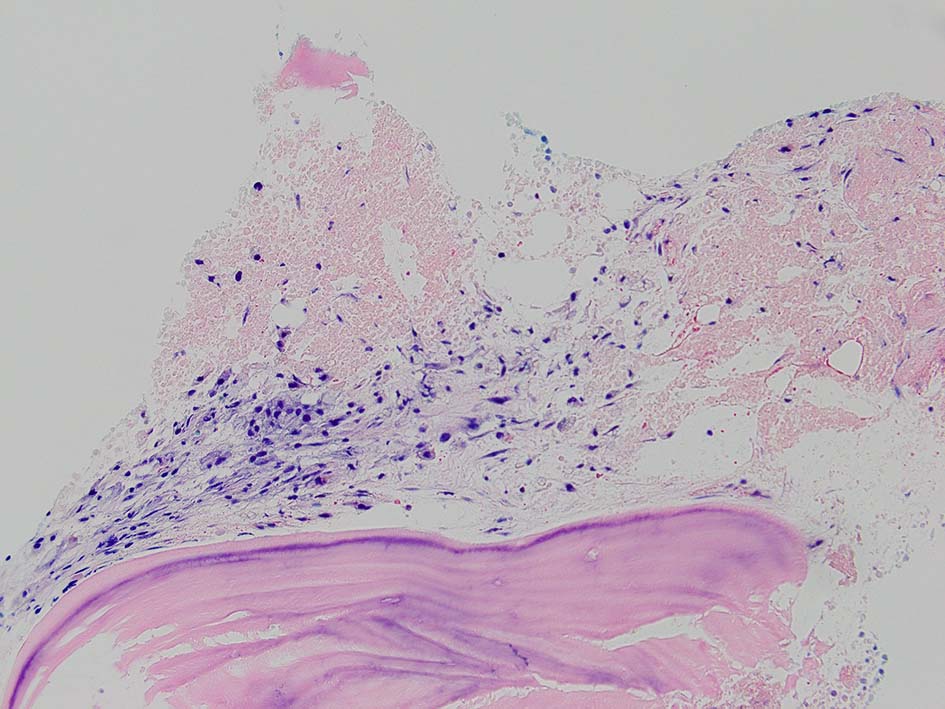

骨髄生検組織所見

骨髄生検組織では骨梁間に壊死に陥った細胞の凝固壊死像が確認できる. 本例では脂肪細胞は消失せず形態が残っている.壊死のあとには, 髄腔に線維化をきたす. 上図には線維化を示し, 右端の図では壊死巣と線維化の境界が観察される.